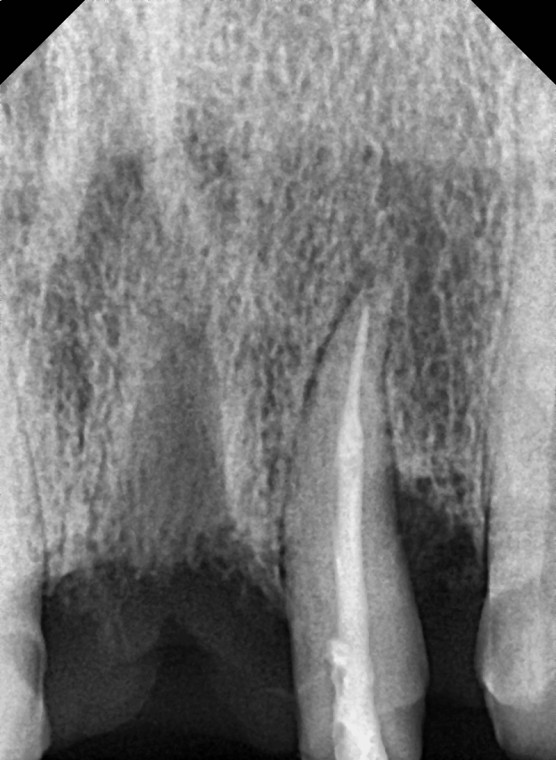

#22 신경노출로 신경치료 진행함.